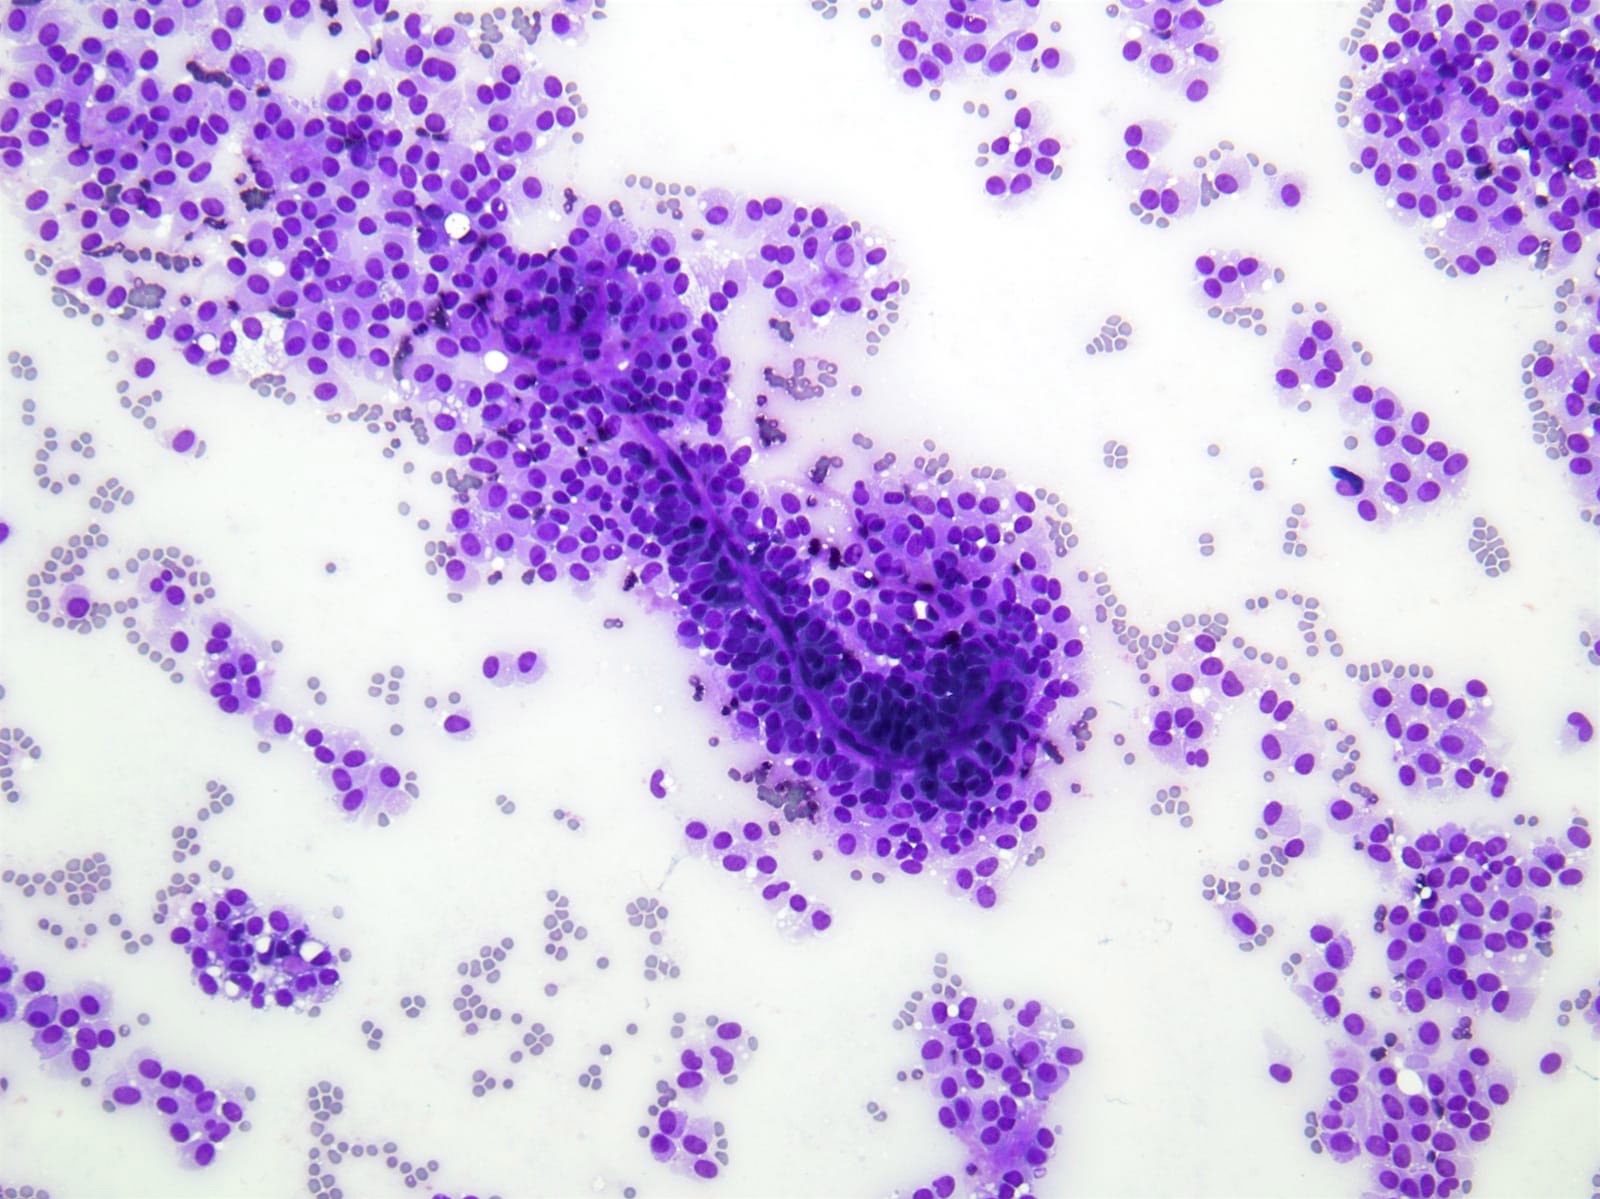

Cytology description

- Cellular smears with delicate papillary fronds

- Tumor cells are usually bland and uniform with a moderate amount of cytoplasm, which usually contains variable sized clear perinuclear vacuoles or cytoplasmic eosinophilic hyaline globules

- Nuclei are round to oval with grooves and finely granular chromatin (J Cytol 2010;27:118, Arch Pathol Lab Med 2017;141:990)

- Cercariform cells, cytoplasmic vacuolation, reniform nuclei, hyaline globules and degenerative features, such as cholesterol crystals, calcifications, foam cells or giant cells, are more commonly seen in solid pseudopapillary neoplasms, compared with acinar cell carcinomas / neuroendocrine tumors (Cancer Cytopathol 2013;121:298)

Cytology images